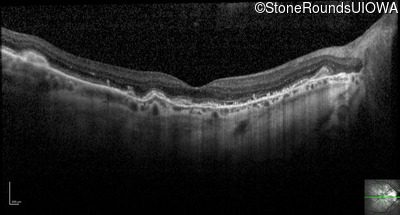

Optical Coherence Tomography - Left - 20/20 -2

Exemplar / OCT Stack

OCT Stack